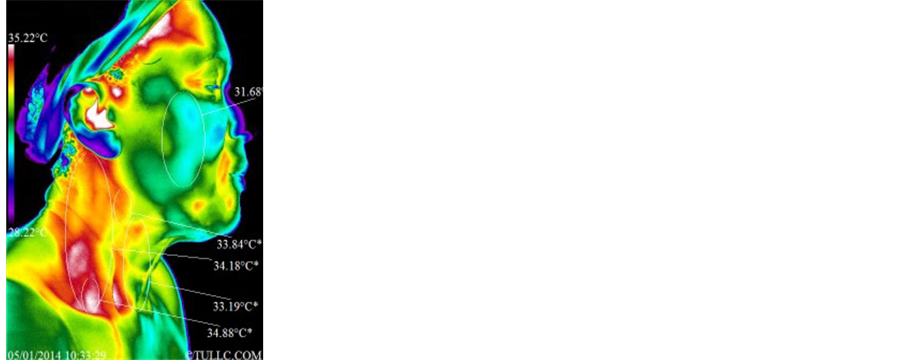

2) Subject E―Female, Caucasian, 55, with bilateral pelvic pain and inner right arm pain from shoulder to hand

Subject E’s facial thermal images were analyzed using a span of 7.01˚C and positioning between 27.76˚C and 34.77˚C. Figure 16 shows that the temperature of the face decreased by a very significant 1.32˚C (32.75˚C - 31.43˚C = 1.32˚C). The temperature of the supraclavicular regions did not change significantly, and the asymmetry of these regions decreased but not significantly. Statistical details of the image markers are presented in Table 1. Figure 17 top images show right lateral side and bottom images show left lateral side of the face before and after the sham-grounding session. Here, the thermal images reveal that the cheeks on both sides cooled off significantly (right side: 31.37˚C - 30.31˚C = 1.06˚C; left side: 31.28˚C - 30.58˚C = 0.70˚C) while the neck became significantly warmer (right side: 33.91˚C - 33.32˚C = 0.59˚C; left side: 33.94˚C - 33.32˚C = 0.62˚C). Note also that the temperature of the right supraclavicular region remained about the same but the left supraclavicular region warmed up, although not significantly. Statistical details are presented in Table 2. Subject E’s full anterior views of the torso are presented in Figure 18. The subject noted pelvic pain on both sides of the abdomen and pain in the inner side of the right arm and shoulder. They are indicated in the left thermal image by the

Figure 16. Subject E facial thermal images before and after a one hour sham-grounding session.

letter “P” superimposed on the regions of pain. The span and positioning of these images is between 27.76˚C and 34.77˚C. The entire anterior torso cooled off except for the axilla and the supraclavicular regions. The temperature of the region around the umbilicus decreased significantly (32.43˚C - 31.54˚C = 0.89˚C). Statistical details are presented in Table 4.

2) Subject E―Female, caucasian, 55, with bilateral pelvic pain and inner right arm pain from shoulder to hand

According to Figure 16, there is a significant drop in temperatures surrounding the orbital/nasal/oral and frontal/temporal regions related to decongestion of lymphatic/venous systems from the head/neck. The face had an average decrease in temperatures of 1.32˚C (32.75˚C - 31.43˚C = 1.32˚C) while the left and right supraclavicular regions had a slight increase by 0.12˚C and 0.25˚C, respectively, suggestive of increases in lymphatic/ venous fluids routed through the subclavian vein. Figure 17 lateral neck image marker evaluations show increased temperatures indicative of a surge of lymphatic/venous fluids routed into the subclavian vein. Posterior-lateral cervicocranial temperatures also appear to be related to myofascial activity that can be influenced by the head elevation with pillow and reclining chair headrest. From Figure 18 after the sham-grounding session, there is an overall abdominal decrease in temperatures except for the stomach/hiatal region. These results appear to be due to improved lymphatic/venous congestion. Diaphragmatic breathing influences unidirectional valves of both lymphatic and venous flow. After the cistern of chyli, a dilated region of the lymphatic system below the diaphragm and prior to the thoracic duct, the diaphragm wall has a significant influence in the forward movement of lymph through the thoracic duct into the left subclavian vein. A significant drop in abdominal temperature of 0.89˚C (32.43˚C - 31.54˚C = 0.89˚C) is suggestive of an improved venous/lymph return that appeared to be due to the subject relaxing in a comfortable reclining chair which made the existing distention more apparent with no indication of an intervention (grounding).